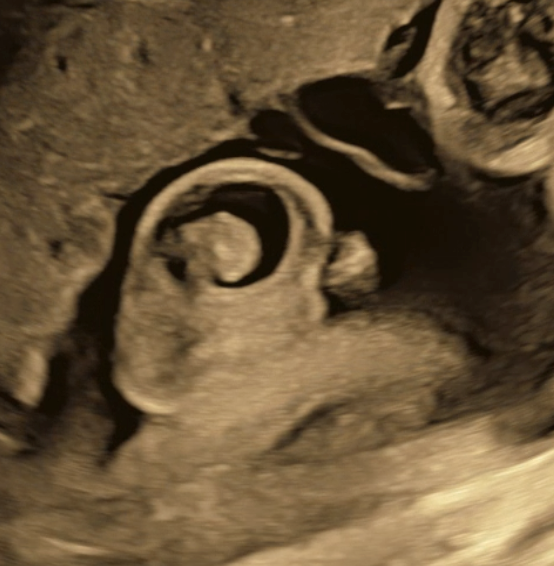

Hình 2: Hình ảnh siêu âm của tràn dịch tinh mạc thuần nhất

Trên siêu âm tiền sản, dấu hiệu chẩn đoán điển hình là một lớp dịch trống âm bao quanh tinh hoàn trong bìu, thành mỏng, không có thành phần đặc, và vẫn nhận diện được tinh hoàn bên trong. Mô tả này cũng phù hợp với y văn về chẩn đoán tiền sản các khối bìu, trong đó hydrocele đơn thuần được nhận biết nhờ hình ảnh dịch trống âm trong bìu. Điều quan trọng là phải phân biệt với thoát vị bẹn-bìu, khi có thể thấy quai ruột hoặc nhu động trong bìu, cũng như với các khối phức tạp khác của bìu thai.